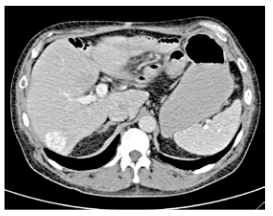

En el posoperatorio temprano, a los cinco días, se realizó una TAC toracoabdominal trifásica como parte de la estadificación adecuada, que mostró metástasis hepáticas en los segmentos III y VI, siendo la primera de 1 x 1 x 1.5 cm y la segunda de 4 x 3 x 2 cm. Estas lesiones no fueron visibles en la primera tomografía debido a que solo se realizó en fase simple, ni tampoco se identificaron a la palpación hepática durante la cirugía. (figuras 5 y 6).

Tomografía axial computarizada trifásica con metástasis hepática en el segmento VI

Tomografía computarizada trifásica corte coronal con metástasis hepática en el segmento III